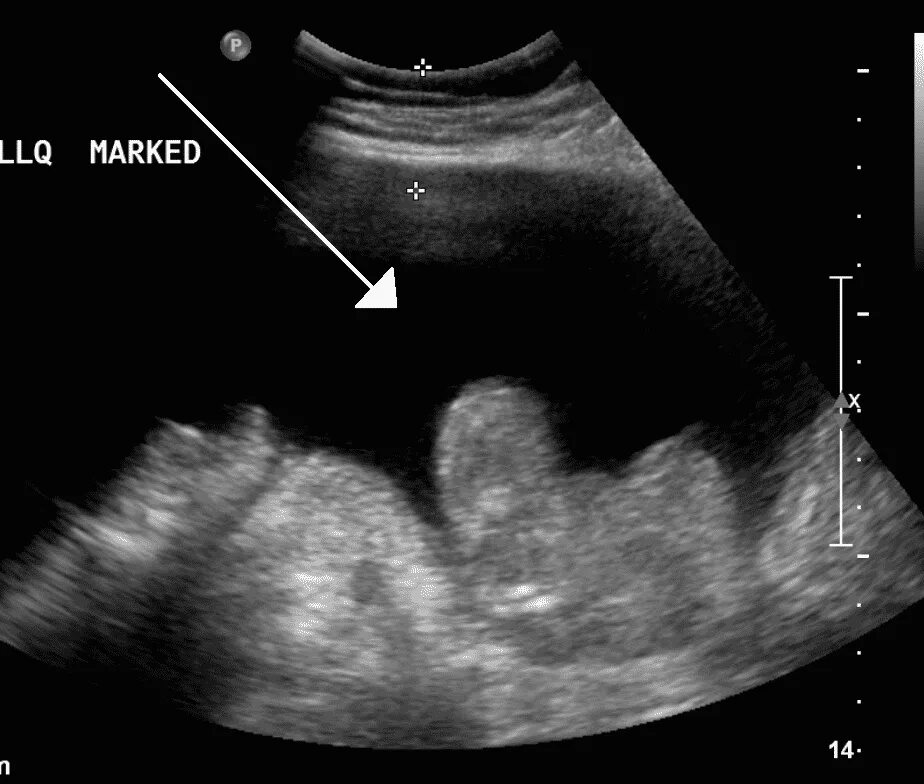

Асцит в малом тазу